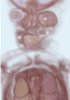

Carnegie Stage 23 (56 post-ovulatory days)

Most embryos at stage 23 are approximately 56-57 postovulatory days old and measure 23-32 mm in length. Distinguishing criteria for this stage include fusion of the eyelids at the medial and lateral margins, clear distinction of the subdivisions of the upper and lower limbs, the forearms appear at or above the level of the shoulders, the superficial vascular plexus of the head is very close to the vertex, and the external genitalia are well developed but not always sufficiently to distinguish the embryo's sex.

(NOTE: These specimens are late stage 23.)

MRI Slice Selector